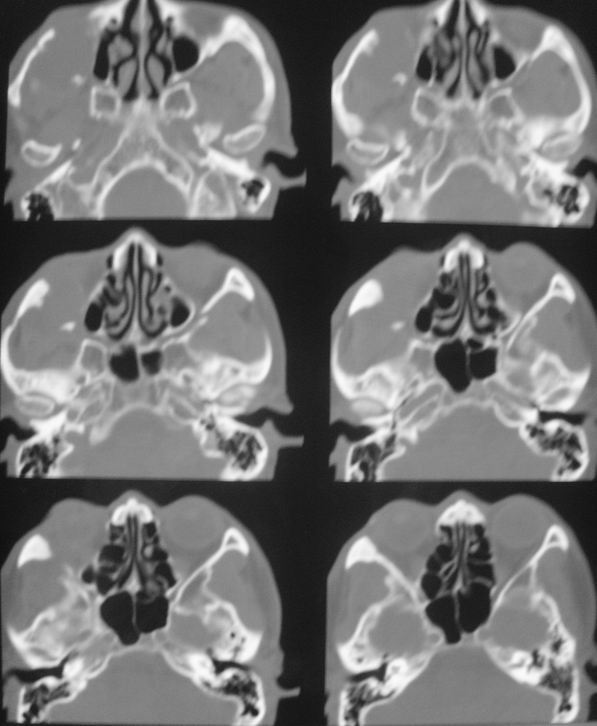

以下是引用zsl6918在2008-5-6 14:41:00的发言:[br]右侧颞下窝内囊性占位(增强未见强化),同侧上颌窦受压变形移位,提示慢性过程。右侧上颌骨局限性吸收破坏,提示良性病变。

以下是引用xuhuihong在2008-5-6 14:57:00的发言:[br]右侧颞下窝内囊性占位(增强未见强化),同侧上颌窦受压变形移位骨质吸收变薄,提示慢性过程。右侧上颌骨局限性吸收破坏,提示良性病变。考虑神经源性肿瘤可能,期待结果。